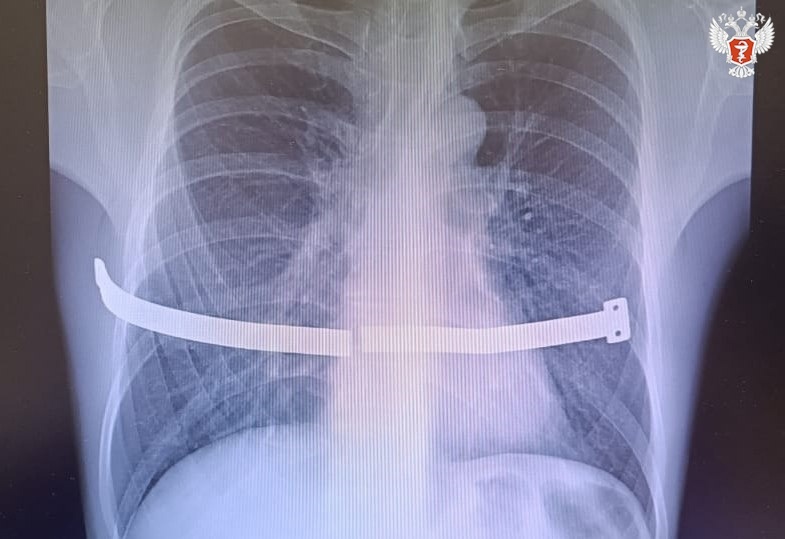

🏥 33-летний мужчина поступил в хирургическое отделение Сургутской клинической травматологической больницы с отломками металлической пластины в грудной клетке.

Конструкцию ему в свое время установили для коррекции воронкообразной деформации груди. Систему обычно удаляют через 2-4 года, но пациент не спешил с операцией, так как, по его словам, никаких неудобств не испытывал. Симптомов и неудобств не было до того времени, пока конструкция не сломалась.

👨⚕ Образовались острые и подвижные края. Один из них упирался в перикард – оболочку сердца. Из-за болевых ощущений мужчина вынужден был обратиться к врачам.